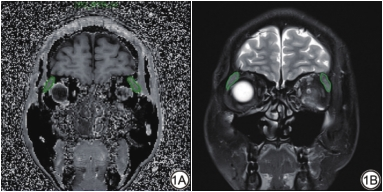

泪腺各定量参数测量的观察者内及观察者间一致性均为优(ICC:0.805~0.903)。活动期组泪腺MTR低于非活动期组,SIR高于非活动期组,两者差异均具有统计学意义(P<0.001,表1,图2)。活动期与非活动期TAO患者各一例影像图像见图3。

MTI通过描述组织中自由氢原子核与结合于大分子上的氢原子核之间的磁化传递过程,从而间接反映组织中大分子的浓度,现已被应用于评估多种疾病的纤维化进程[18, 24]。Jiang等[25]研究发现MTI可监测肾动脉狭窄继发的肾脏纤维化,且MTR与肾脏纤维化程度呈正相关。Li等[19]研究发现,MTR可随克罗恩病患者肠纤维化程度的增加而升高,进而区分炎症性及纤维性肠管狭窄。在本研究中,非活动期TAO患者的泪腺MTR显著高于活动期TAO患者。考虑到TAO的病理特征,笔者认为泪腺MTR的升高可能与非活动期泪腺组织纤维化进程有关[4,26]。泪腺MTR与CAS的低度负相关可能进一步提示,随着疾病活动性的降低,泪腺纤维化程度进展。另一方面,活动期组TAO患者泪腺SIR值显著高于非活动期组,与既往研究结果一致[5],可能与活动期患者泪腺组织水肿、炎性细胞浸润,在FS-T2WI图像上表现为泪腺形态肿大、信号增高有关[27]。泪腺SIR与CAS的弱正相关也进一步验证了泪腺组织炎性改变可随疾病活动性的增加而进展。